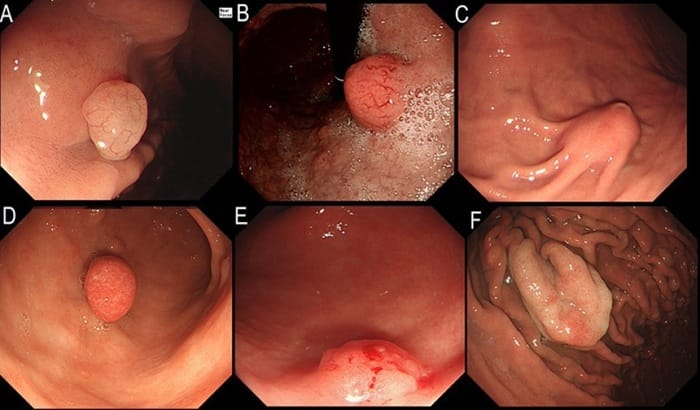

Thông thường, polyp dạ dày nên cắt khi kích thước >0,5cm, dạng u tuyến hoặc có nguy cơ ung thư hóa, nhằm ngăn tiến triển thành ung thư. Ngược lại, polyp nhỏ, lành tính hoặc liên quan đến vi khuẩn HP có thể chỉ cần điều trị và theo dõi định kỳ 6–12 tháng. Quyết định cắt hay không do bác sĩ đánh giá sau thăm khám và sinh thiết.

Chỉ cắt polyp dạ dày có kích thước lớn, nguy cơ ung thư hóa cao

Polyp dạ dày nên cắt nếu có kích thước lớn, dạng u tuyến, nguy cơ ung thư cao hoặc gây triệu chứng như loét, chảy máu, tắc nghẽn và hội chứng đa polyp.